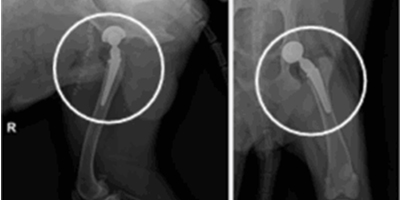

인공 고관절 치환술 Total Hip Replacement (THR) 고관절

고관절 인공관절 수술은 고관절 이형성증, 대퇴두 무혈성 괴사, 외상성 고관절 탈구 등으로 관절이 비가역적으로 손상된 경우에 시행됩니다.

FHO(Femoral Head Ostectomy)와 같은 보존적 또는 대체 수술만으로는 충분한 기능 회복이 어려운 경우, 통증 완화와 정상적인 관절 기능 회복을 위해 인공 고관절 치환술이 효과적인 선택이 될 수 있습니다.